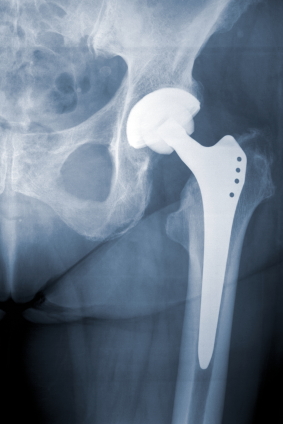

Hip implants are supposed to last for at least 15 years. According to figures, no more than 5% of hip implant patients should require revision surgery within 5 years. However with the DePuy implant, over 13% of patients so far have required revision surgery due to the failure of the implant.

Other than failing completely, some of the other problems include loosening of implanted cups, dislocation, lack of bone growth into implanted cups and metalosis. There have also been reports of inflammation or tissue damage from the metal shavings. This can be very nasty leading to the tissue surrounding the implant to die and rot.